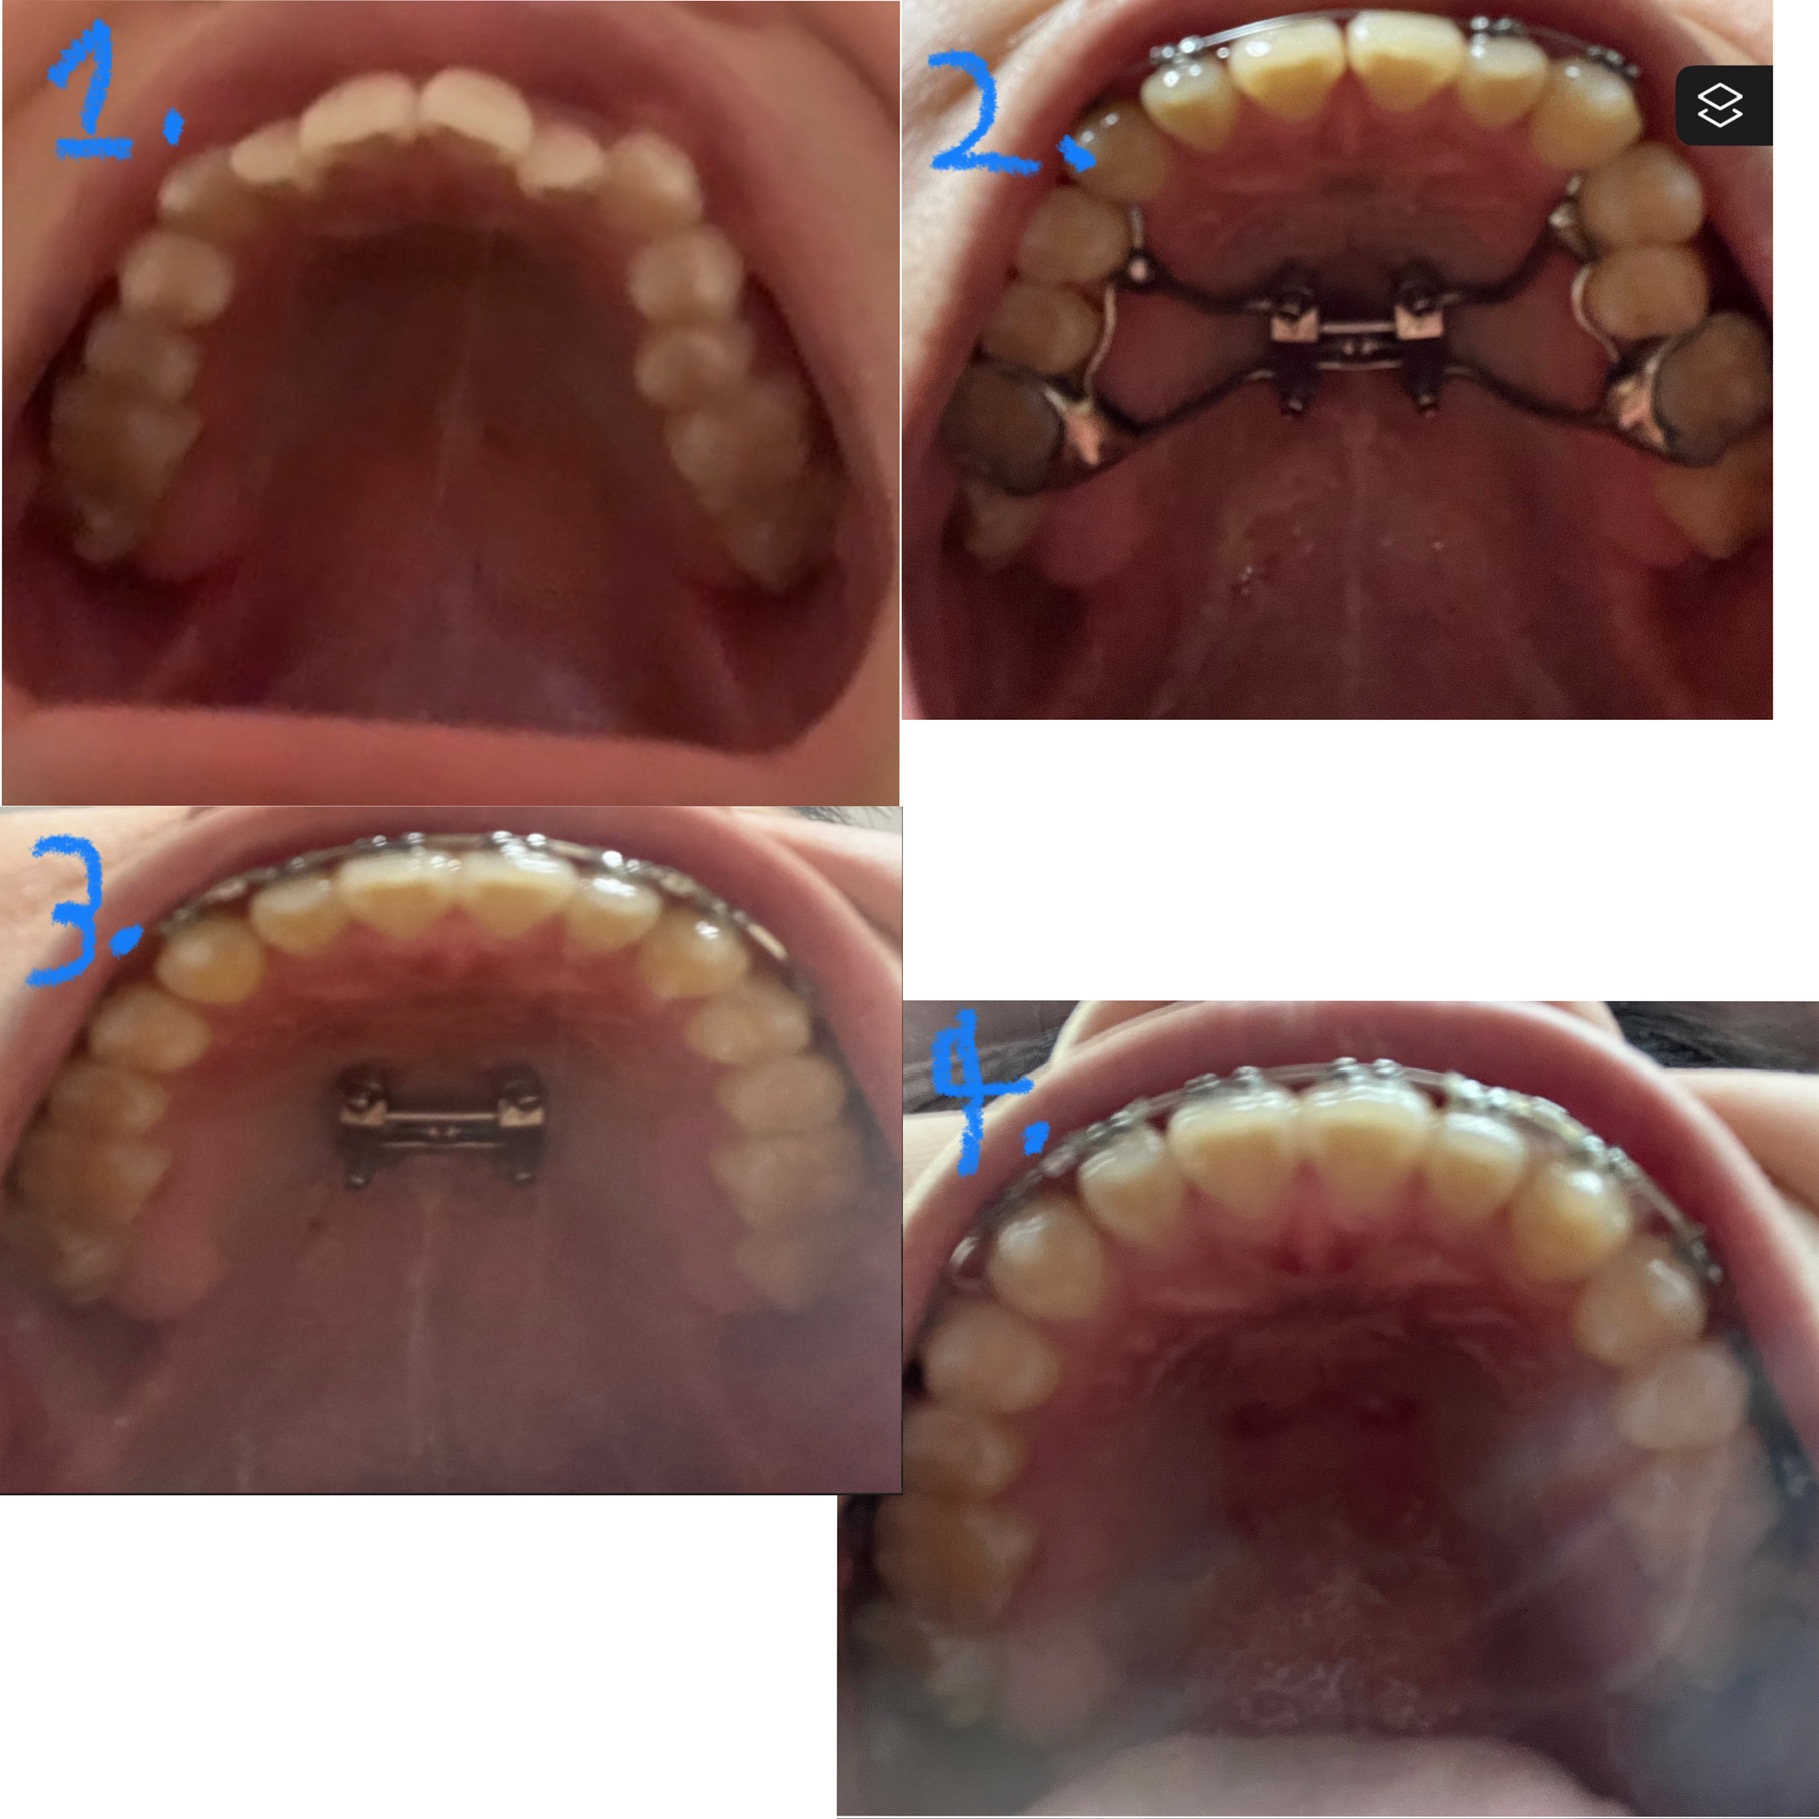

I got my MSE around a year and a half ago, recently having gotten the MSE removed. I don’t know how much I have expanded (in mms), but if anyone knows the expander model, I have expanded to the max limit (of turns) of the MSE. My braces and MSE was just a prerequisite for DJS and I will update again next month after I undertake it.

I got my MSE around a year and a half ago, recently having gotten the MSE removed. I don’t know how much I have expanded (in mms), but if anyone knows the expander model, I have expanded to the max limit (of turns) of the MSE. My braces and MSE was just a prerequisite for DJS and I will update again next month after I undertake it.View attachment 4435272